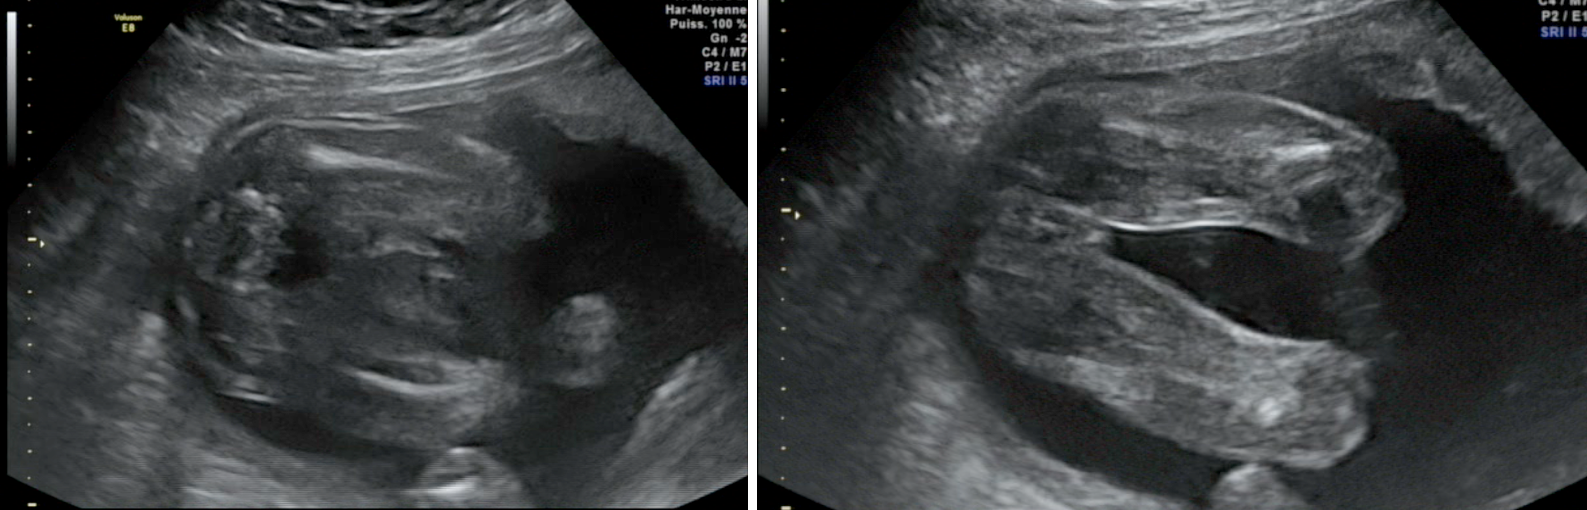

12 Les signes qui doivent attirer votre attention;Toute bourse aiguë exige une évaluation urgente, dans l'hypothèse d'une torsion menaçant une gonade Elle est avant tout clinique, mais peut comporter une utilisation sélective d'examens complémentaires, dont souvent l'échographie, à confier à un opérateur entraîné (1) Torsion du pédicule spermatique (TPS) La douleur3 Comment prendre soin de la peau de votre bébé métis ?

Atlas Echographique D Une Bourse Aigue Chez L Enfant L Essentiel Pour S En Sortir Pdf Free Download

La Bourse Aigue De L Enfant Correlations Radiocliniques Urofrance